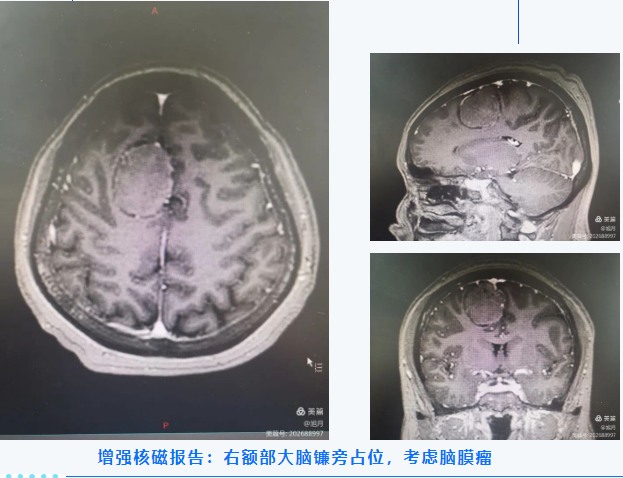

57岁女性患者,因间断头痛3月、加重10天入院,于外院查核磁提示:“大脑中线部占位性病变”,为进一步治疗来我院就诊。

考虑患者正是享福的年纪,患者本人手术意愿强烈。兴安盟人民医院神经外科团队了解病情后立即组织团队成员进行讨论,考虑若不手术切除肿物,肿物逐渐增大,可能出现瘤卒中甚至脑疝、危及生命的情况。最终决定在全身麻醉下行“神经导航下颅内病损切除术”,术前MDT:请感染科、耳鼻喉科、麻醉科及心内科会诊,评估手术及麻醉风险。手术过程顺利,术中肿瘤切除彻底,止血充分,术区周围重要血管脑组织保护良好。